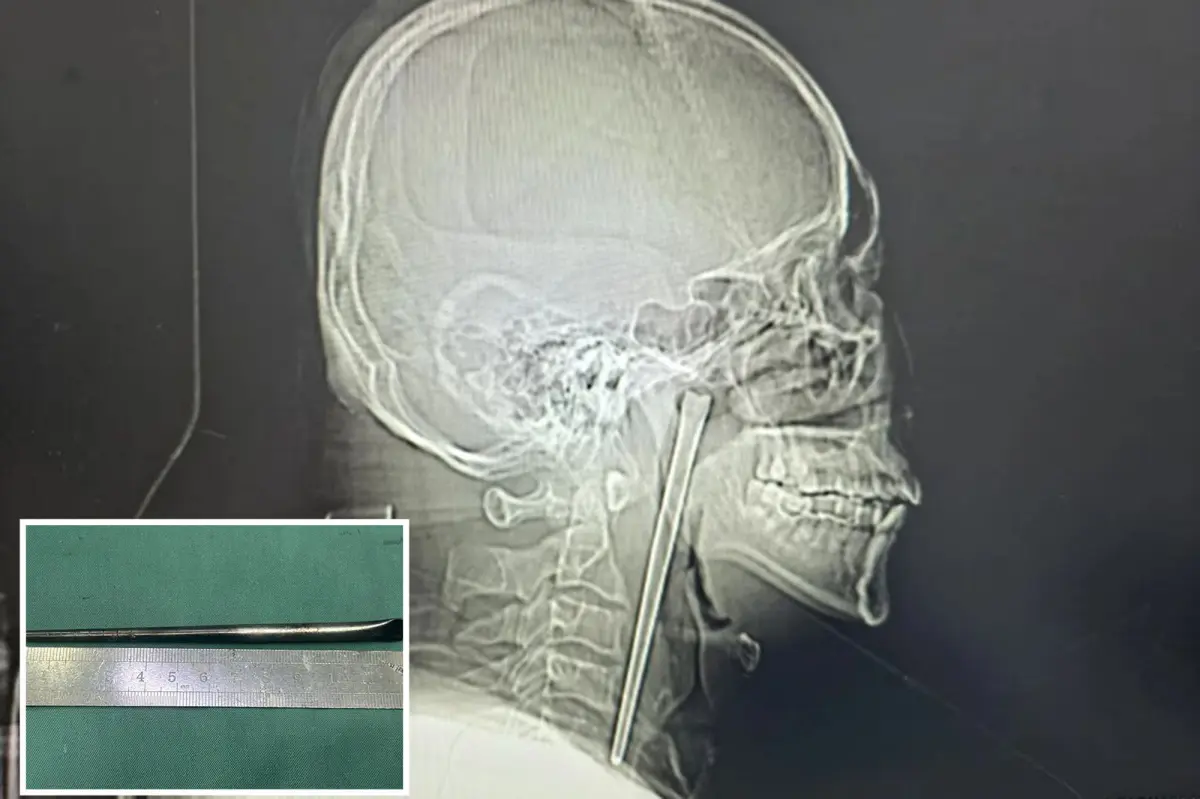

A drunk man in China swallowed a metal chopstick while eating dinner eight years ago — and decided to leave it lodged in his throat until a surgeon finally yanked it out last month, according to a jaw-dropping report.

The “alcoholic” patient, identified only as Mr. Wang, went in for a check-up shortly after gulping down the five-inch utensil in 2018 but refused to have it removed, according to a hospital case study published in March.

Surgeons performed a minimally invasive operation to remove the obstructive object via Wang’s mouth instead of slicing open his neck, according to the hospital’s report.